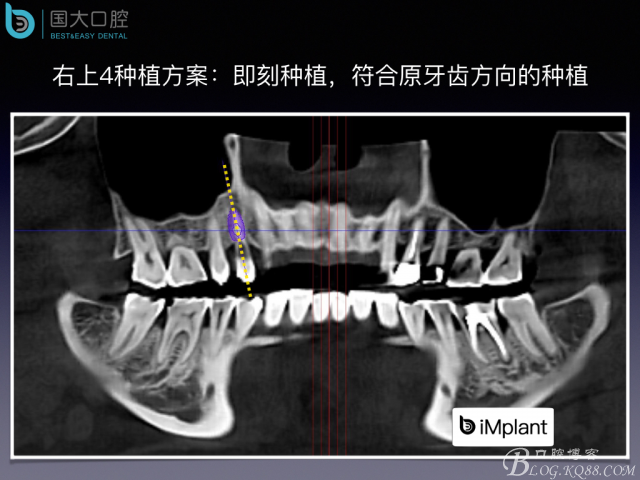

來源于國大口腔 邵現(xiàn)紅醫(yī)生發(fā)表的博文